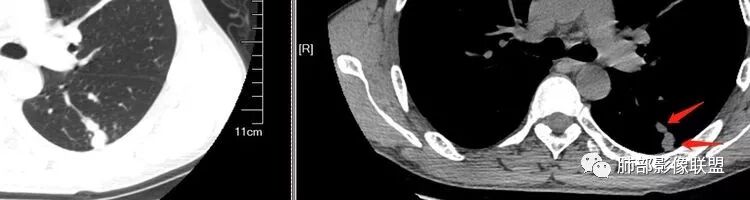

南边:

这是我首先把它定在炎性,附近有一些小卫星灶,我还是倾向结核放在前面,待排恶性肿瘤。刚才有老师考虑隐球,这个就不太支持,因为它的长轴是沿支气管过来的,这明显就不是隐球特点。附近有一些小卫星灶,我还是倾向一个结核的可能性大。

尘缘:沿支气管由外向内的爬行,常规分析还是考虑结核,小细胞癌待排。

支气管树爬行征这个观点是袁怀平老师提出来的。当时提出了一个观点,就是说支气管是通畅的。

现在就是支气管树爬行征的认定问题,就是关于支气管通与不通?如果堵塞,在哪个区域堵塞?

支气管树爬行征就是肉芽肿性病变,不过它是沿着支气管周围间质往里面走的。我们以前认定支气管要通畅的,但是我们读了隐球菌发现,包括肺炎性肺癌,你就发现外围的病变往内带进展,可以支气管堵塞,例如隐球菌有个特点非常明显的,一个大片状影,支气管在中近端堵塞。我们反推过来,结核也可以这样变化;支气管爬行征原来是要求支气管通畅,改良为支气管可以通畅,也可以在中间堵塞。

该如何判断支气管树爬行征,还需要大宗数据进行观察总结。